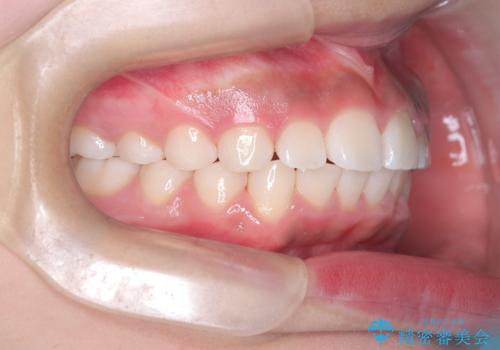

- 患者様は前歯の突出を主訴に来院されました。診査の結果、上顎の前歯が前方に傾斜しており、口元がやや突出して見える状態でした。一般的にこのようなケースでは抜歯矯正が選択肢となりますが、**患者様が抜歯を希望されなかったため、非抜歯での遠心移動(奥へ動かす治療)を計画しました。そのため、リンガルアーチ(歯の裏側に装着する装置)とTAD(歯科矯正用アンカースクリュー)**を併用し、上顎の歯を後方へ移動させながら噛み合わせを整える方法を選択しました。